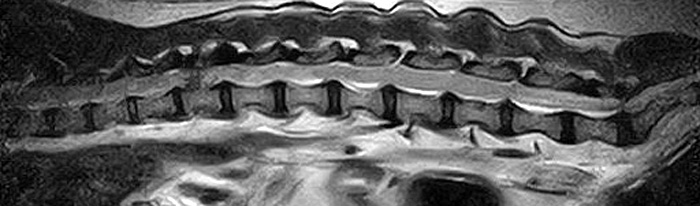

市外の先生からフレブルちゃん両後肢麻痺グレード3でMRI検査及び手術依頼でご紹介がありました。MRI検査で第12‐13胸椎間椎間椎間板ヘルニア、右側優位な圧迫と診断し手術となりました。